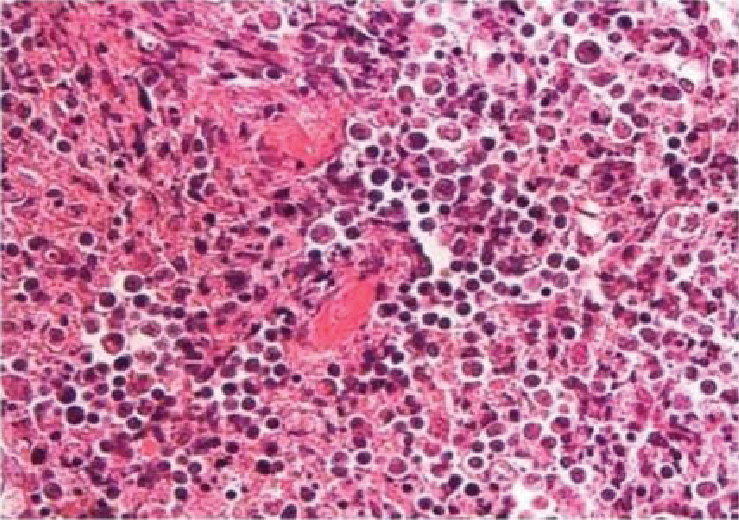

Ultrasonography (USG) of abdomen did not show any lymphadenopathy. USG left cervical region showed few enlarged level V cervical lymph nodes. Patient underwent cervical lymph node biopsy, which revealed histiocytic necrotizing lymphadenitis suggestive of KFD (Figs. 1 and 2).

Figure 2. Lymph node biopsy showing numerous foci of necrosis with apoptotic bodies and scattered histiocytes. Absence of acute inflammatory infiltrate and hematoxylin bodies are suggestive of Kikuchi’s disease.